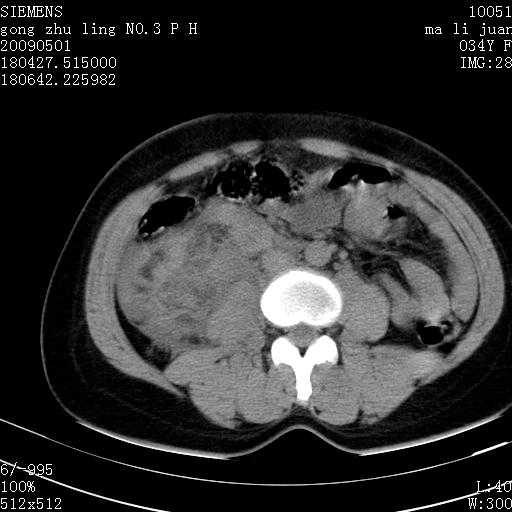

标题: CT19733:右肾碎裂

青年女性,骑摩托车摔伤。

右肾碎裂伤,包膜下血肿。

术中仅见右肾碎裂,肾蒂血管未见断裂。

支持右肾碎裂伤,包膜下血肿。

支持右肾破裂伴包膜下血肿。